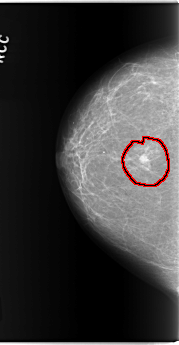

FILE: C_0143_1.RIGHT_MLO.OVERLAY

TOTAL_ABNORMALITIES 1

ABNORMALITY 1

LESION_TYPE MASS SHAPE IRREGULAR MARGINS ILL_DEFINED

ASSESSMENT 5

SUBTLETY 5

PATHOLOGY MALIGNANT

TOTAL_OUTLINES 1

BOUNDARY